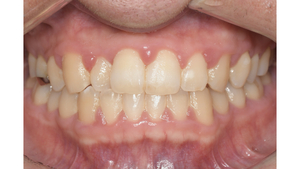

before

症例

after

基本情報

年齢・性別 32歳・男性

主訴 主訴:歯ぐきから出血する

治療部位:全顎

治療内容 「全顎」

歯周基本治療(歯周精密検査、スケーリング、OHI、SRP)

治療期間 約3ヶ月

治療費 歯周基本検査:約600円(保険診療3割負担)

スケーリング、OHI:約2,000円(保険診療3割負担)×2回

SRP、OHI:約1,500円(保険診療3割負担)×4回

歯周精密検査:約1,200円(保険診療3割負担)×2回

合計金額13,000円

(2025年2月現在)

担当者所見 初診時は、写真を見て分かるように、歯ぐきが赤く腫れていました。

また、歯周病の検査では、全体的に歯と歯の間の部分の歯周ポケットが4ミリあり、全体の約81%から出血が認められました。

出血量も多く、歯ぐきに触れた瞬間に出血しました。

レントゲンで骨のレベルがしっかりとあることが確認できました。

そのため、ご自身で正しい歯磨きを継続することで改善すると考えました。

歯周基本治療を経て、再度検査した結果、歯周ポケットはほぼ3ミリ以下に改善しました。左下7番の残存した歯周ポケットは、隣の親知らずを抜いたため経過観察します。

出血率は約4%まで改善し、出血量も点状で少なくなりました。

今後は右上2番、右下3番の歯ぐきの発赤の改善と、出血率0%を目指して、定期検診でメンテナンスしていきます。